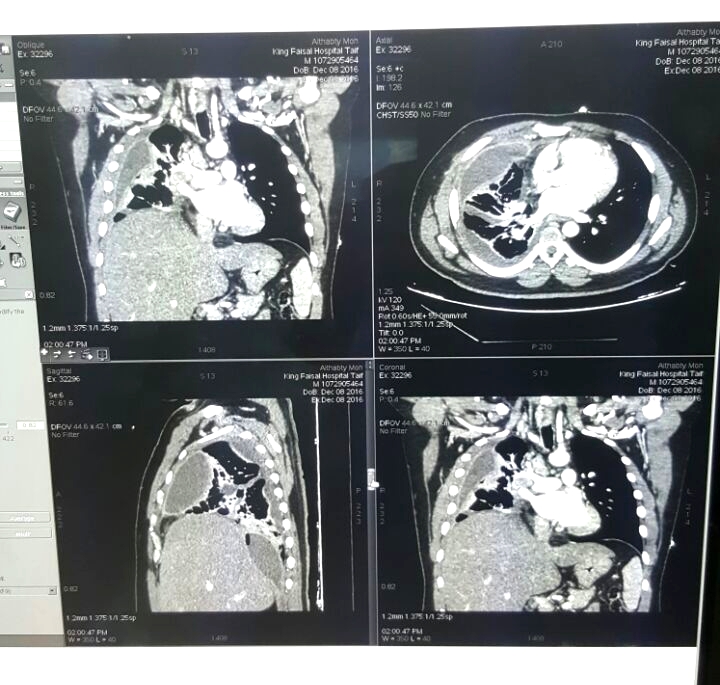

وقال استشاري جراحة المناظير والصدر بمستشفى الملك عبد العزيز التخصصي بالطائف، وعضو هيئة التدريس بكلية الطب بجامعة الطائف، الدكتور محمد عيد محفوظ، إن المريض أُدخِل من قبل الأخصائي المناوب بمجمع الملك فيصل بالطائف، وأودع العزل نتيجة الاشتباه بإصابته بفيروس كورونا، وأظهرت الفحوصات وجود تقيُّح شديد ومتعدّد بالصدر، مع التهاباتٍ والتصاقاتٍ شديدية بالرئة اليمنى، وضيقٍ بالتنفس، مع ارتفاعٍ بدرجة الحرارة، وأعراض تسمُّم بالدم.

وأضاف أنه تم التعامل فورًا مع الحالة، وخضع المريض لمنظارٍ جراحي متقدم عن طريق فتحتين تم من خلالهما تنظيف الصدر، وتحرير الرئة اليمنى من الالتصاقات وتجمّعات القيح حولها، وعمل الغسيل اللازم للصدر، مع وضع أنابيب تروية صدرية.